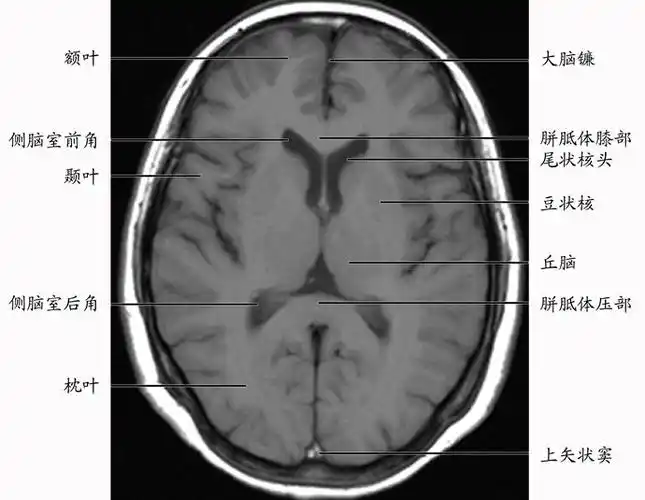

正常颅脑影像解剖图医学影像图